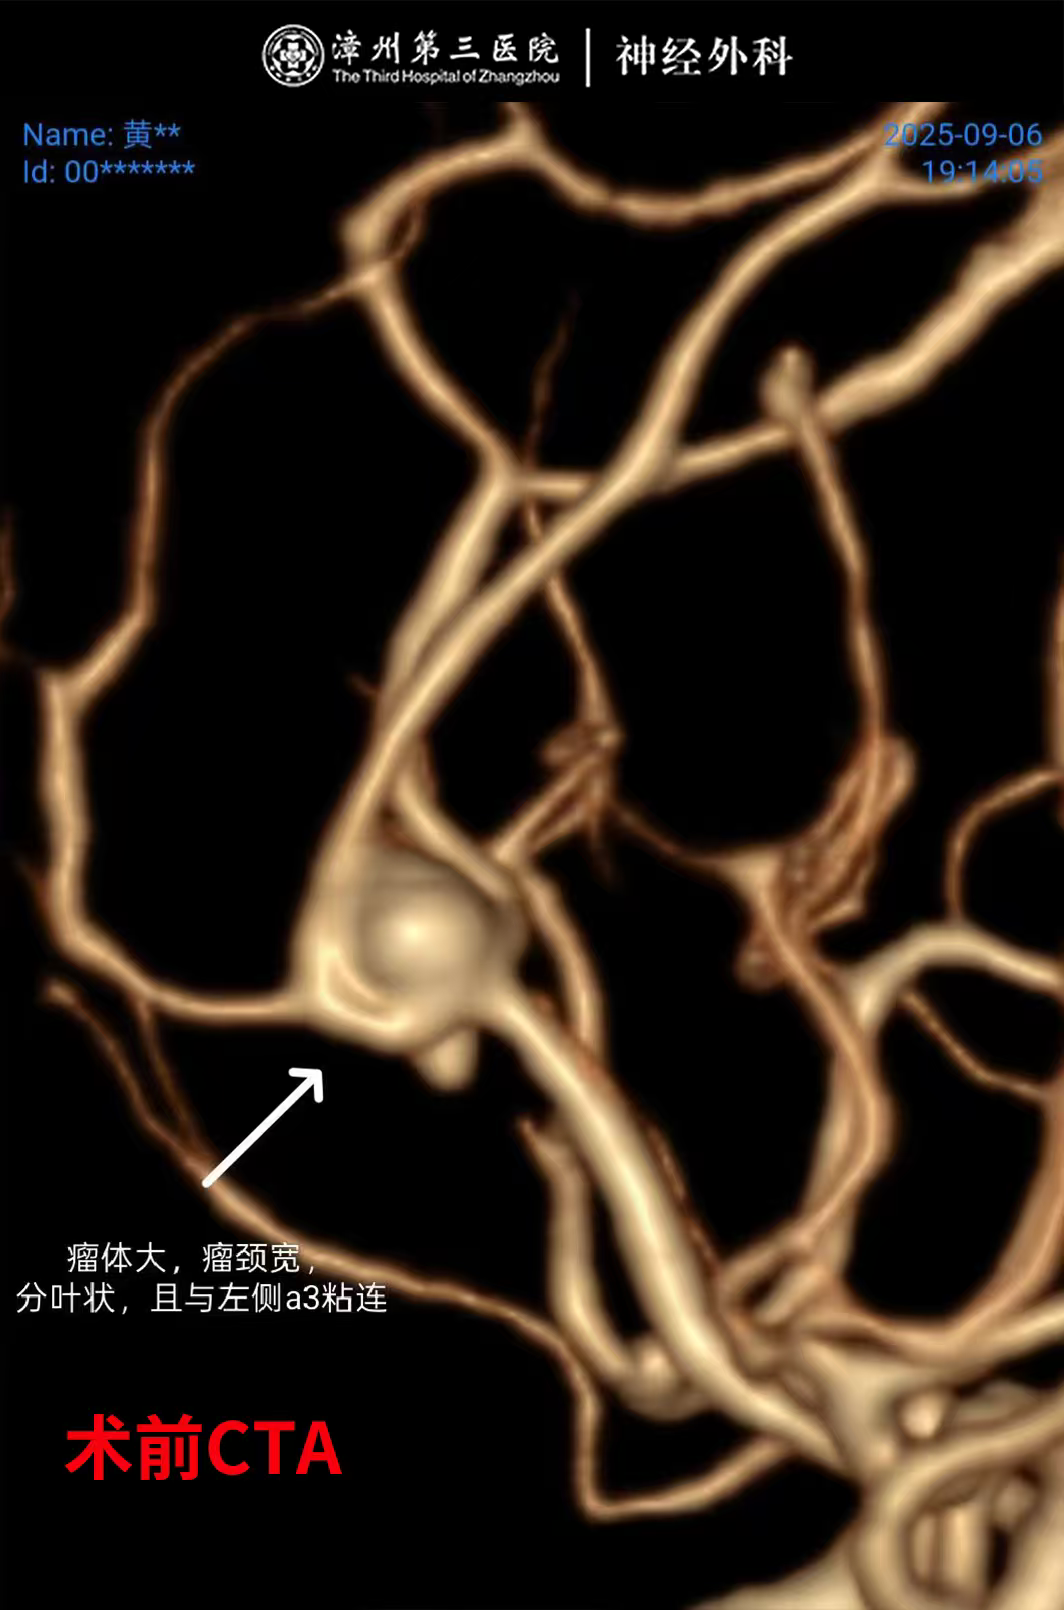

检查结果一出来,所有人的心都揪紧了:左侧大脑前动脉瘤破裂出血,且这颗动脉瘤是双侧A₂共干、宽颈,分叶状的大瘤体,动脉瘤已经破裂引起蛛网膜下腔出血,极有可能出现二次破裂导致病情急剧加重,危及生命。

神经外科团队第一时间紧急会诊,深知这颗“复杂炸弹”的凶险:位置深、形态不规则,宽颈分叶的结构,且与周围的血管关系密切,让手术夹闭难度陡增,加上深夜突发,必须与时间赛跑,神经外科团队经过详细的术前讨论,迅速敲定“纵裂入路分区并列组合夹闭动脉瘤”。主刀医生神经外科卢炜鹏主任凭借多年深耕脑血管病领域的经验,在显微镜下精准操作,逐一分开动脉瘤周围复杂结构,将分叶的瘤体分区夹闭,同步引流颅内积血、置入颅内压监测装置。整个手术紧张有序,最终成功“拆弹”,未伤及周围正常组织。